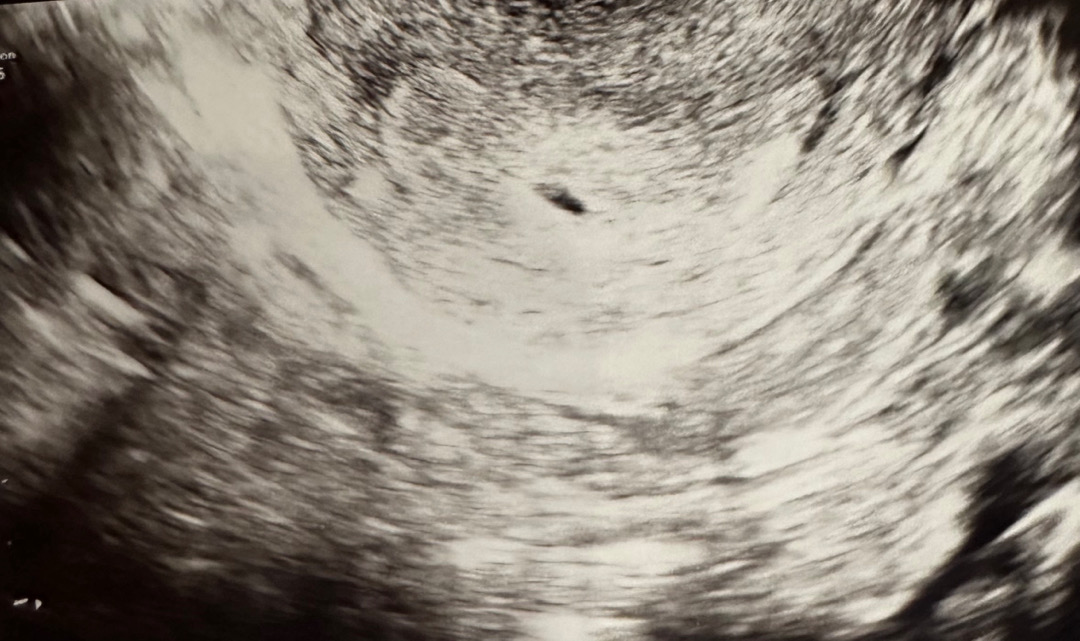

아기집

금요일에 4주 5일때 아기집 0.4cm구용 담주 목욜에 병원갈껀데 난황이 보일시기일까여??

다음주 가시면 보일거같아요~